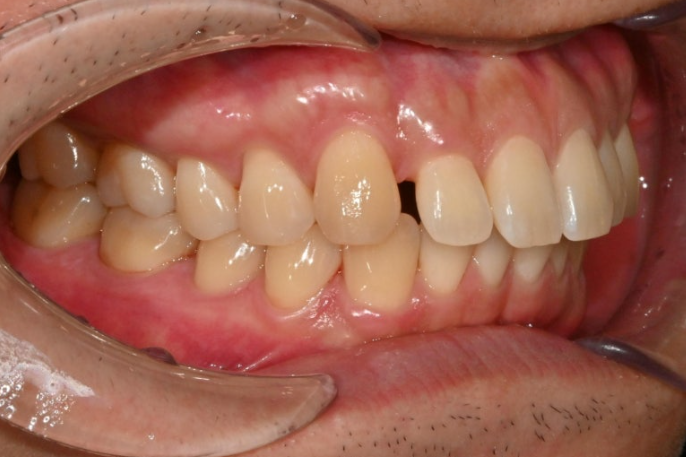

파란 화살표와 같이 물리는 상태를 가위교합이라고 합니다.

맨 뒤 큰 어금니에 흔하게 보이는 부정교합입니다.

위 어금니는 배열에서 바깥으로 나가있고

아래 어금니는 안으로 쓰러져 있습니다.

경미한 총생과 중심선 불일치, 가위교합, 벌어짐, 과개교합 문제가 있는 상황입니다.